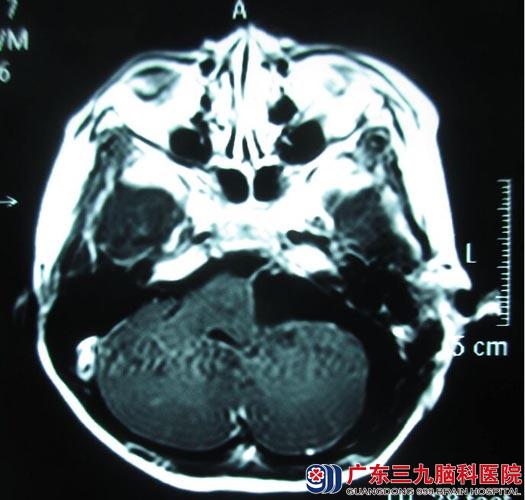

转诊到广东三九脑科医院综合神经外科,行头颅MR检查显示:左侧桥小脑角区占位性病变,大小约51mm×43mm×55mm,脑干、左侧桥壁及左侧小脑半球明显受压,考虑听神经瘤可能。